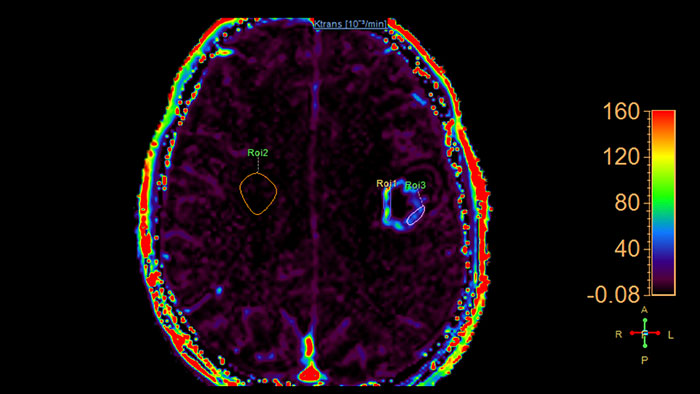

Lesion characterization by reviewing vascular leakage

MR Permeability helps perform measurements, such as measuring the leakage of gadolinium chelates into the extra-vascular extracellular space (EES). The most important use relates to oncology of the prostate and brain. This tool calculates parametric maps such as Ktrans and Kep which is related to tracer kinetics behavior.

Benefits